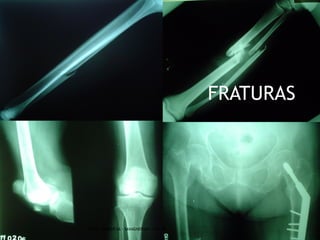

FRATURAS